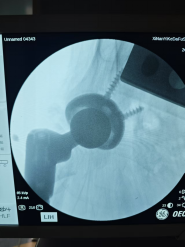

"老人骨质疏松严重,又有低血糖、心脏问题,千万小心再次跌倒!"出院时医生的叮嘱言犹在耳。然而7月的一天,邱婆婆再次摔倒——这次是右侧髋部着地,剧痛让她瞬间无法站立。更糟的是,检查发现不仅骨盆骨折,此前植入的固定钢钉竟因冲击力穿破股骨头刺入盆腔!

"情况比想象中凶险得多。"主刀医生尹一然教授解释,这枚"跑偏"的钢钉紧邻大血管,稍有不慎就会引发大出血;而老人除了高龄,还合并骨质疏松、重度贫血、肾功能不全、心脏问题等16种基础疾病,手术风险极高。

8月8日,一场精密的"生命保卫战"打响。由骨科尹一然教授领衔,联合麻醉科、心血管内科、肾内科等专家制定方案:既要取出刺入盆腔的钢钉,又要解决髋臼缺损和骨量流失难题,还要确保新关节稳固。

先小心翼翼取出嵌在盆腔的钢钉,避免损伤血管;

将患者自身修剪后的股骨头骨质填补到髋臼破损处,重建"地基";

植入特制加长股骨柄假体,像"钢筋"一样牢牢固定新关节。